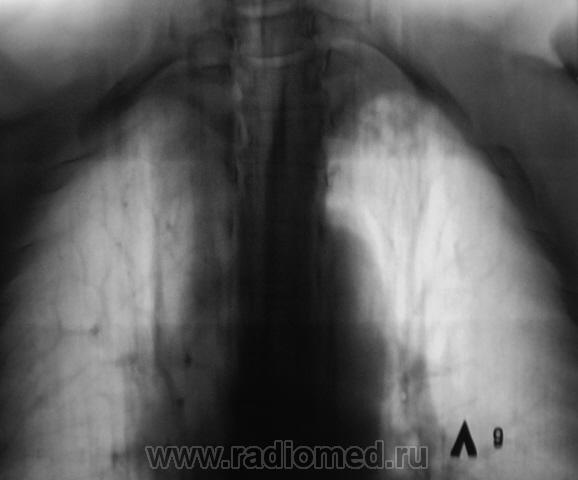

Пол пациента: Мужской пол Тип патологии: Инфекция Область исследования: Грудная клетка и верхние дыхательные пути Методы исследования: Rg При расшифровке флюорограмм пациент взят "на контроль". Известно, что на учете пациент не состоял, со слов пациента "ничем не болел". Произведено стандартное исследование - рентгенография и томография в стандартных срезах. Ваше мнение коллеги? Пнд, 23/11/2009 - 19:34 #1 Глазков Игорь А... Не на сайте Был на сайте: 1 год 2 месяцев назад Зарегистрирован: 19.12.2008 - 20:41 Публикации: 1597 инфильтративного туберкулёза слева в верхней доле Прийди к Себе

инфильтративного туберкулёза слева в верхней доле